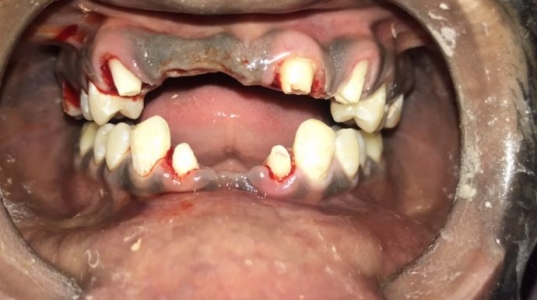

At Pranjal Dental Clinic, we offer a wide range of advanced dental treatments in Greater Noida to ensure complete oral health and beautiful smiles. Our services include root canal treatment, dental implants, smile designing, teeth whitening, cosmetic dentistry, tooth extraction, and painless dental care. With modern technology and expert care by Dr. Pranjal Sirohi, we provide safe, effective, and comfortable dental solutions for patients of all ages.